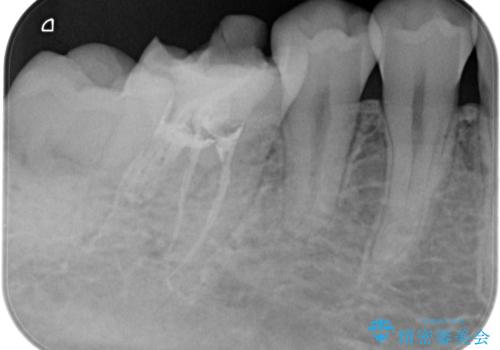

【根管治療】ラバーダムと顕微鏡を用いた治療

- 奥歯の治療の継続を主訴に来院された患者様です。

他院にて根管治療を行ったそうですが、ラバーダムを使用していなかったため、クラウン修復の前に当院の治療を希望され受診されました。

根管内に充填されている材料は、スカスカの状態で簡単に除去ができました。

術後1年経過を見ていますが、問題なく良好な経過をたどっています。